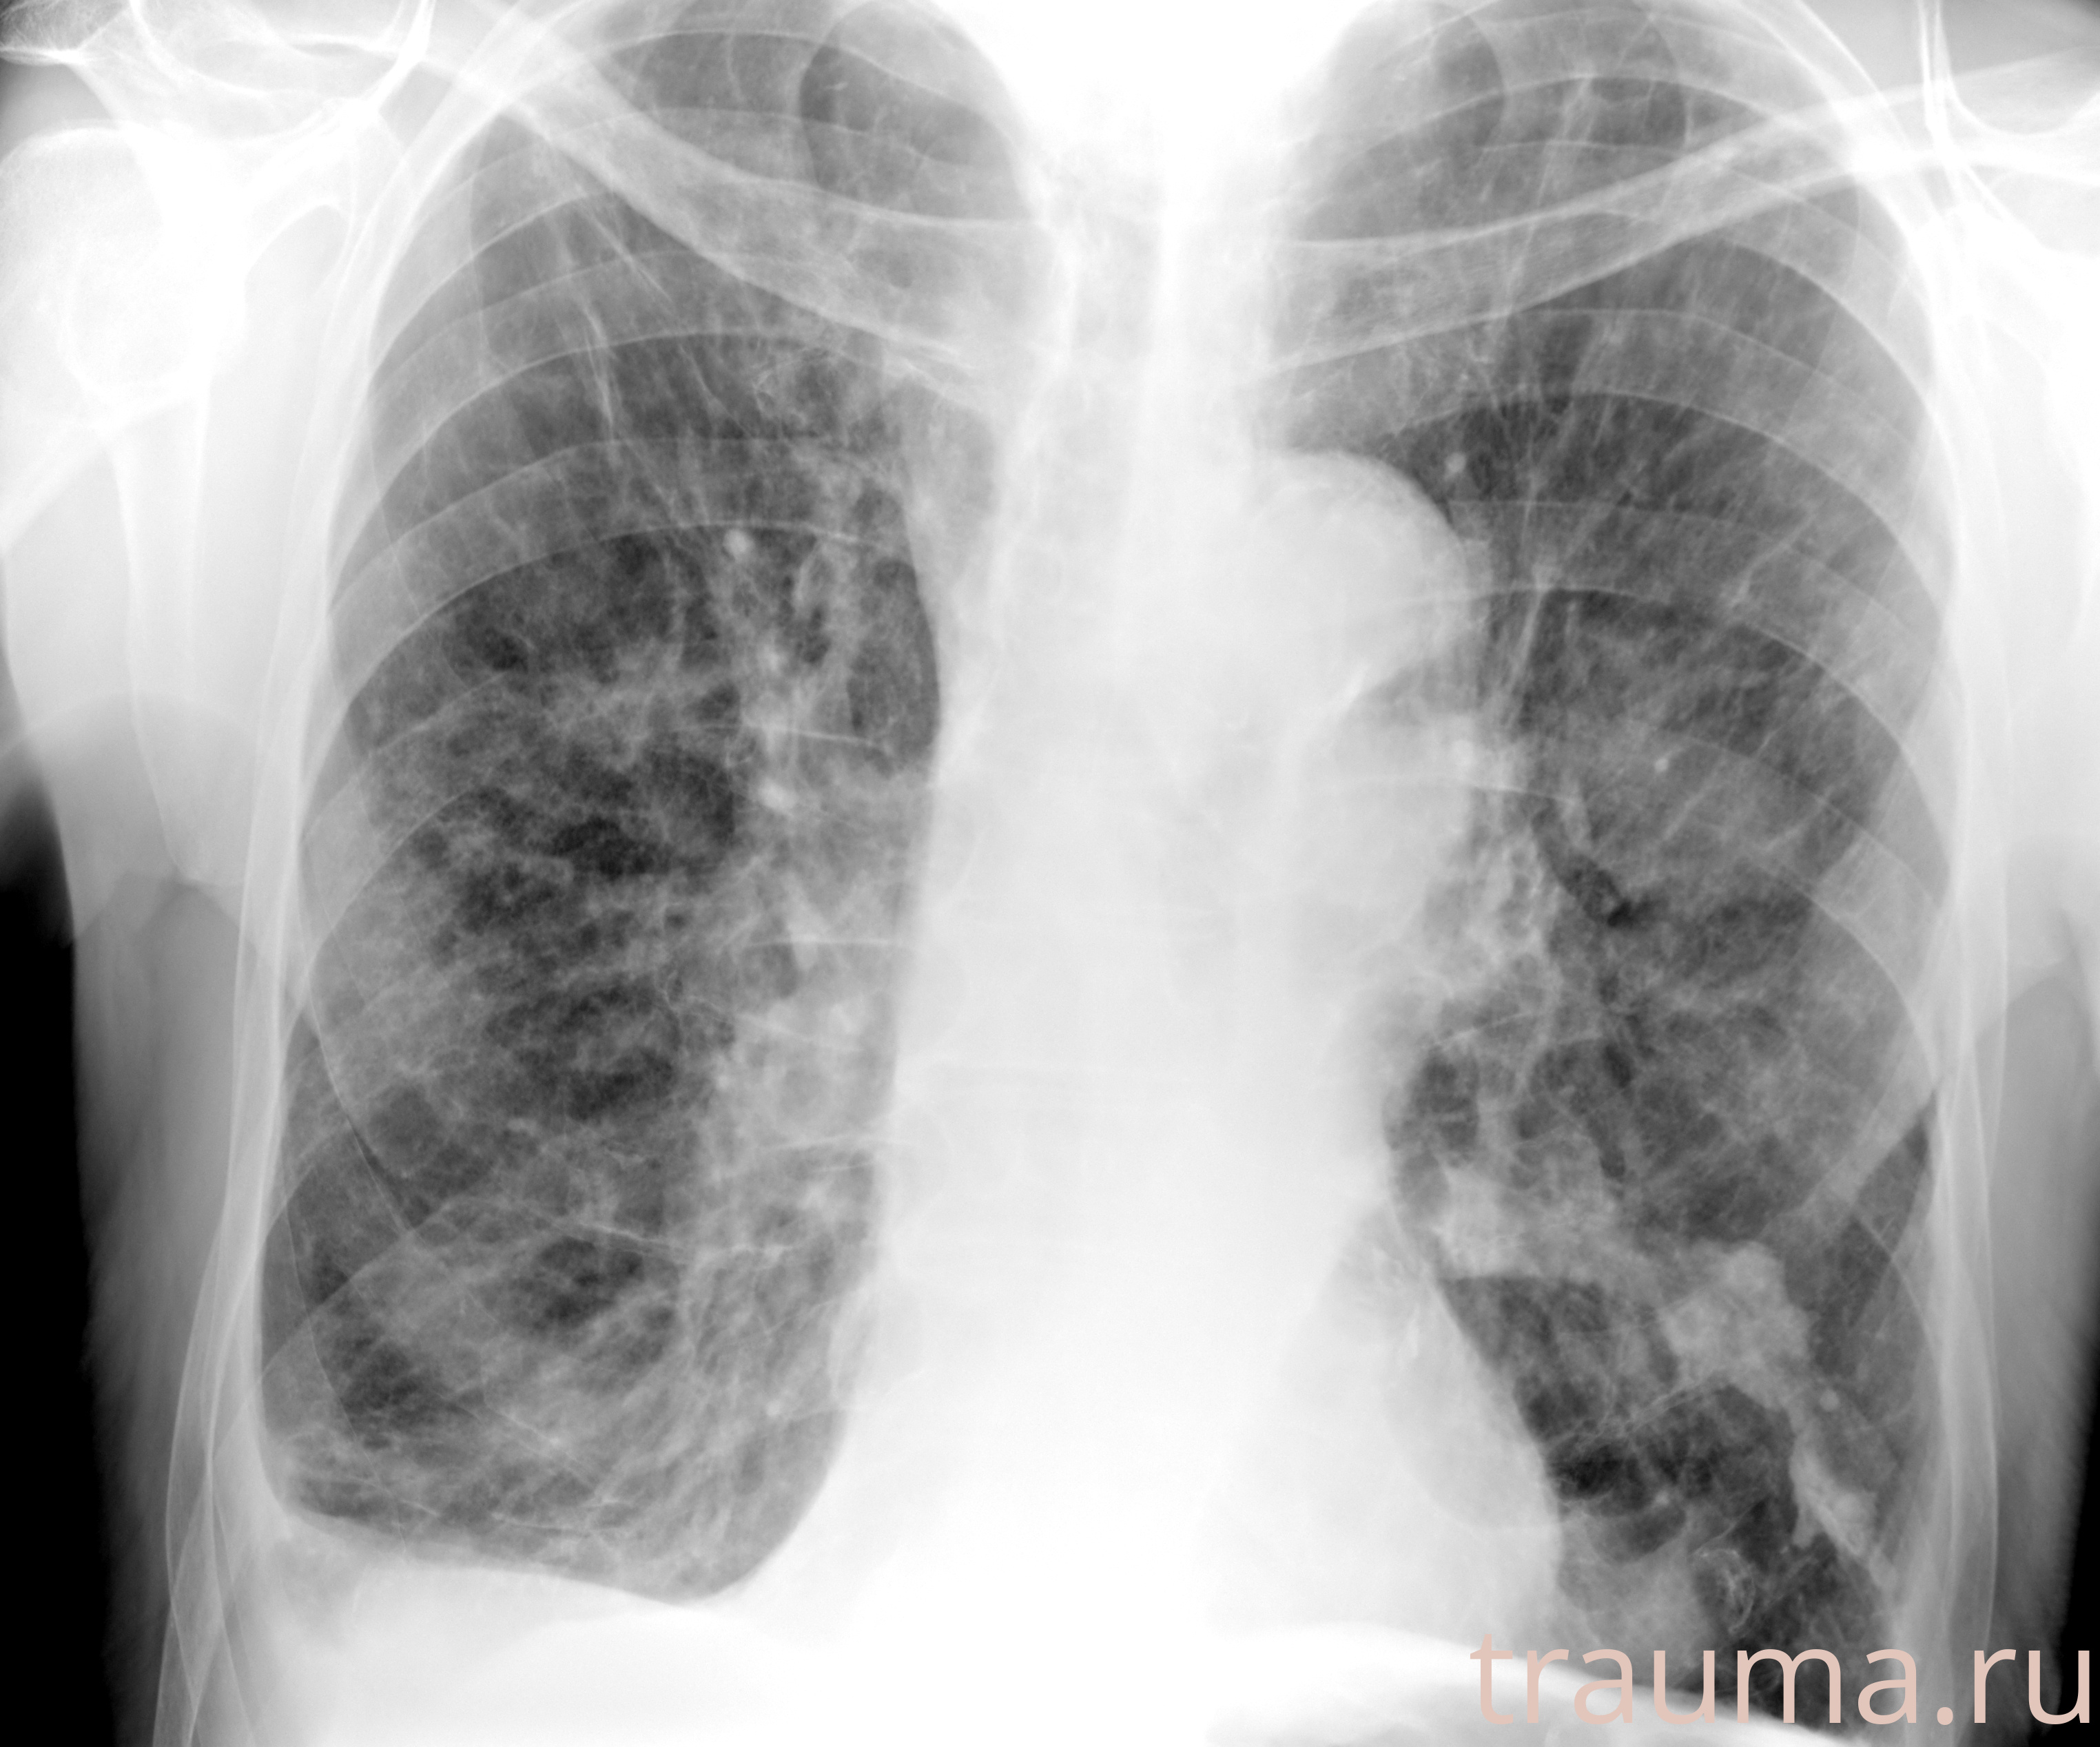

Рентгенограммы

Рентген на дому: по вашему адресу приезжает врач-рентгенолог, травматолог-ортопед с мобильным рентгеновским аппаратом, проводит диагностику травмы или заболевания, делает необходимые рентгенограммы, дает рекомендации по дальнейшему лечению. Получить качественные снимки в домашних условиях возможно благодаря уникальной методике, разработанной МосРентген Центром для института  Склифосовского